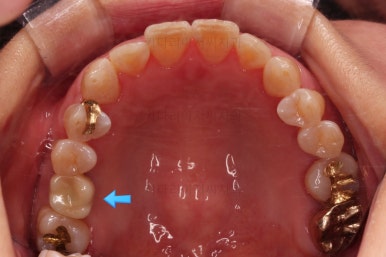

적절한 공간이 확보되었다고 판단되면 임플란트를 식립합니다.

임플란트가 뼈에 단단히 붙은 몇개월의 시간동안 교정치료를 좀 더 마무리 해주고요.

임플란트 머리 부분까지 완성이 되었습니다.

교정치료와 임플란트를 병행하면서 치아 빠진 부위가 다행히 잘 마무리가 되었네요.

전후사진을 비교해보겠습니다.

쓰러진 치아도 원위치로 만들어 기능을 회복시켜주었고, 임플란트도 1개로 마무리를 할 수 있었어요.